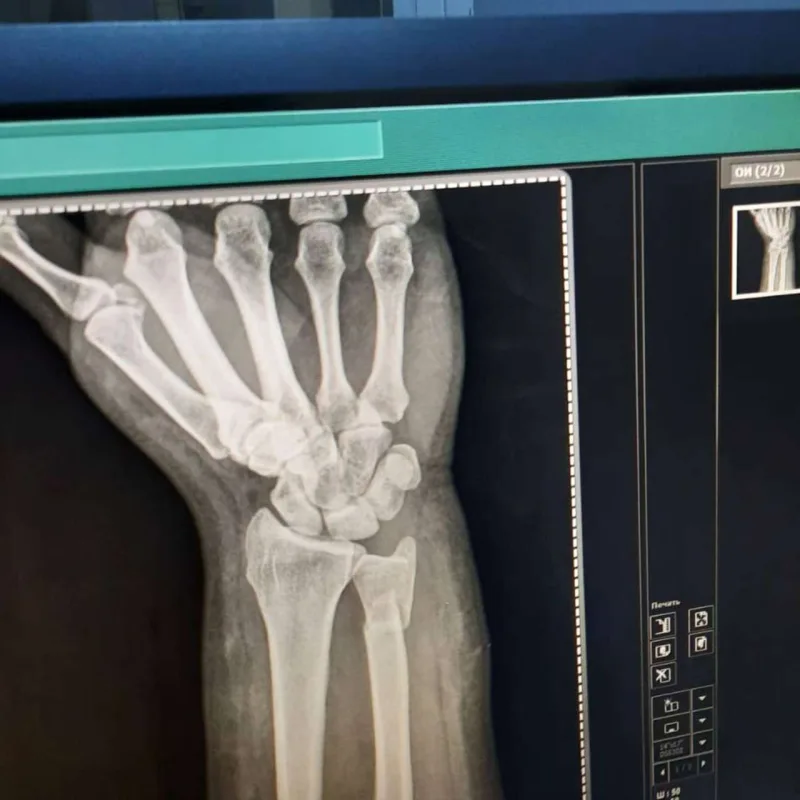

Tanınmış aparıcı Aytən Səfərovanın başına iş gəlib.

OLAY yazır ki, aparıcının bilək sümüyü sınıb. Bu barədə Səfərova instaqramda məlumat yayıb. O bildirib ki, bu günlərdə anası ağır əməliyyata hazırlaşır:

“Çox çalışdım ki, könlümü fərəh tutum, fikirləşdiyimi büruzə verməyim, özümü “sındırmayım”, lakin sümüyümü sındırdım. Həkimlər vaxtında müdaxilə etdilər.  Hələ ki, ağrıkəsicisiz mümkün deyil, amma biz güclü qadınıq. İnşallah bu da keçər. Özünüzü qoruyun”.

Aytən biləyini sındırdı - Fotolar Aytən biləyini sındırdı - Fotolar Aytən biləyini sındırdı - Fotolar Aytən biləyini sındırdı - Fotolar